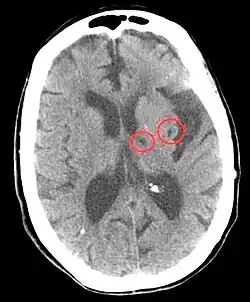

| CT scan of two lacunar strokes. | |